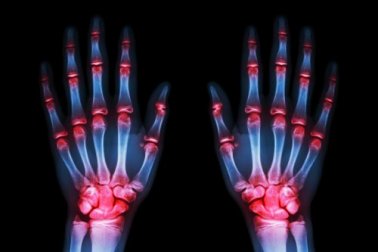

- Arthrose ist an den Händen sehr häufig anzutreffen (70%).

- Wie wir alle wissen, gehen wir meist erst dann zum Arzt, wenn wir an Schmerzen leiden und “nicht mehr können”. Schmerzen in der Hand sind sehr intensiv und unangenehm. Die Hände schlafen dabei in der Nacht oft ein und es kommt zu kleinen Verformungen.